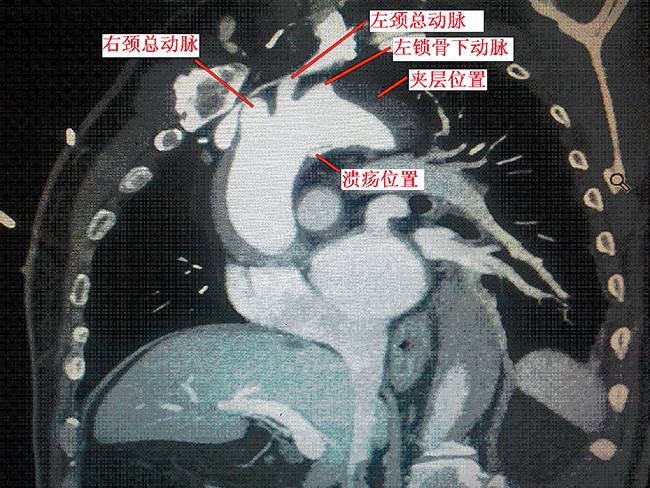

2014年12月4日心脏大血管外科为一名主动脉巨大溃疡合并B型夹层的患者,成功实施腔内隔绝手术(左颈总动脉和左锁骨下动脉双开窗),术后造影显示:左颈总动脉和左锁骨下动脉通畅良好。夹层、溃疡消失,无内漏。查询,双开窗技术在腔内隔绝手术治疗夹层应用中,是河南省首例。该项手术的成功开展,开创了心脏外科高难度介入手术的先例,继去年我科为B型夹层(破口靠近左锁骨下动脉),行左锁骨下动脉单开窗技术,又上了一个新台阶。

该患者男性,47岁,患者主诉胸背部疼痛3小时。主动脉CTA提示:主动脉夹层(主动脉弓部小弯侧穿透性溃疡形成合并B型夹层)。由于患者溃疡位于做左锁骨下动脉下方小弯侧,传统方法,封闭左锁骨下动脉或采用“烟囱”技术,容易使患者术后头痛左上肢活动耐量下降,内漏发生律高。南阳市中心医院心脏大血管外科杨侃主任聚集科室精英骨干,讨论病案,决定突破了传统手术方法,采用介入双开窗技术手术,在导管室全麻下行主动脉腔内隔绝术,支架前端0.5cm向后开一3x1cm窗,术中支架紧贴无名动脉远端释放,开窗部位与左劲总动脉左锁骨下动脉精确对位。术后溃疡完全封闭,头臂血管血流通畅,假腔消失。本例介入手术,突破了传统手术方法,取支架开窗手术优点,避免了封闭左锁骨下动脉及烟囱内漏等传统弊端。

此例手术的难点在于,精确判定溃疡位置和三个头臂血管的关系,开窗部位与头臂血管的精确对位。本例手术的成功完成,标志着我院心脏大血管外科在治疗复杂B型夹层上又上了一个新的台阶,开创了河南省心脏外科介入手术先河,达到了国内领先水平。